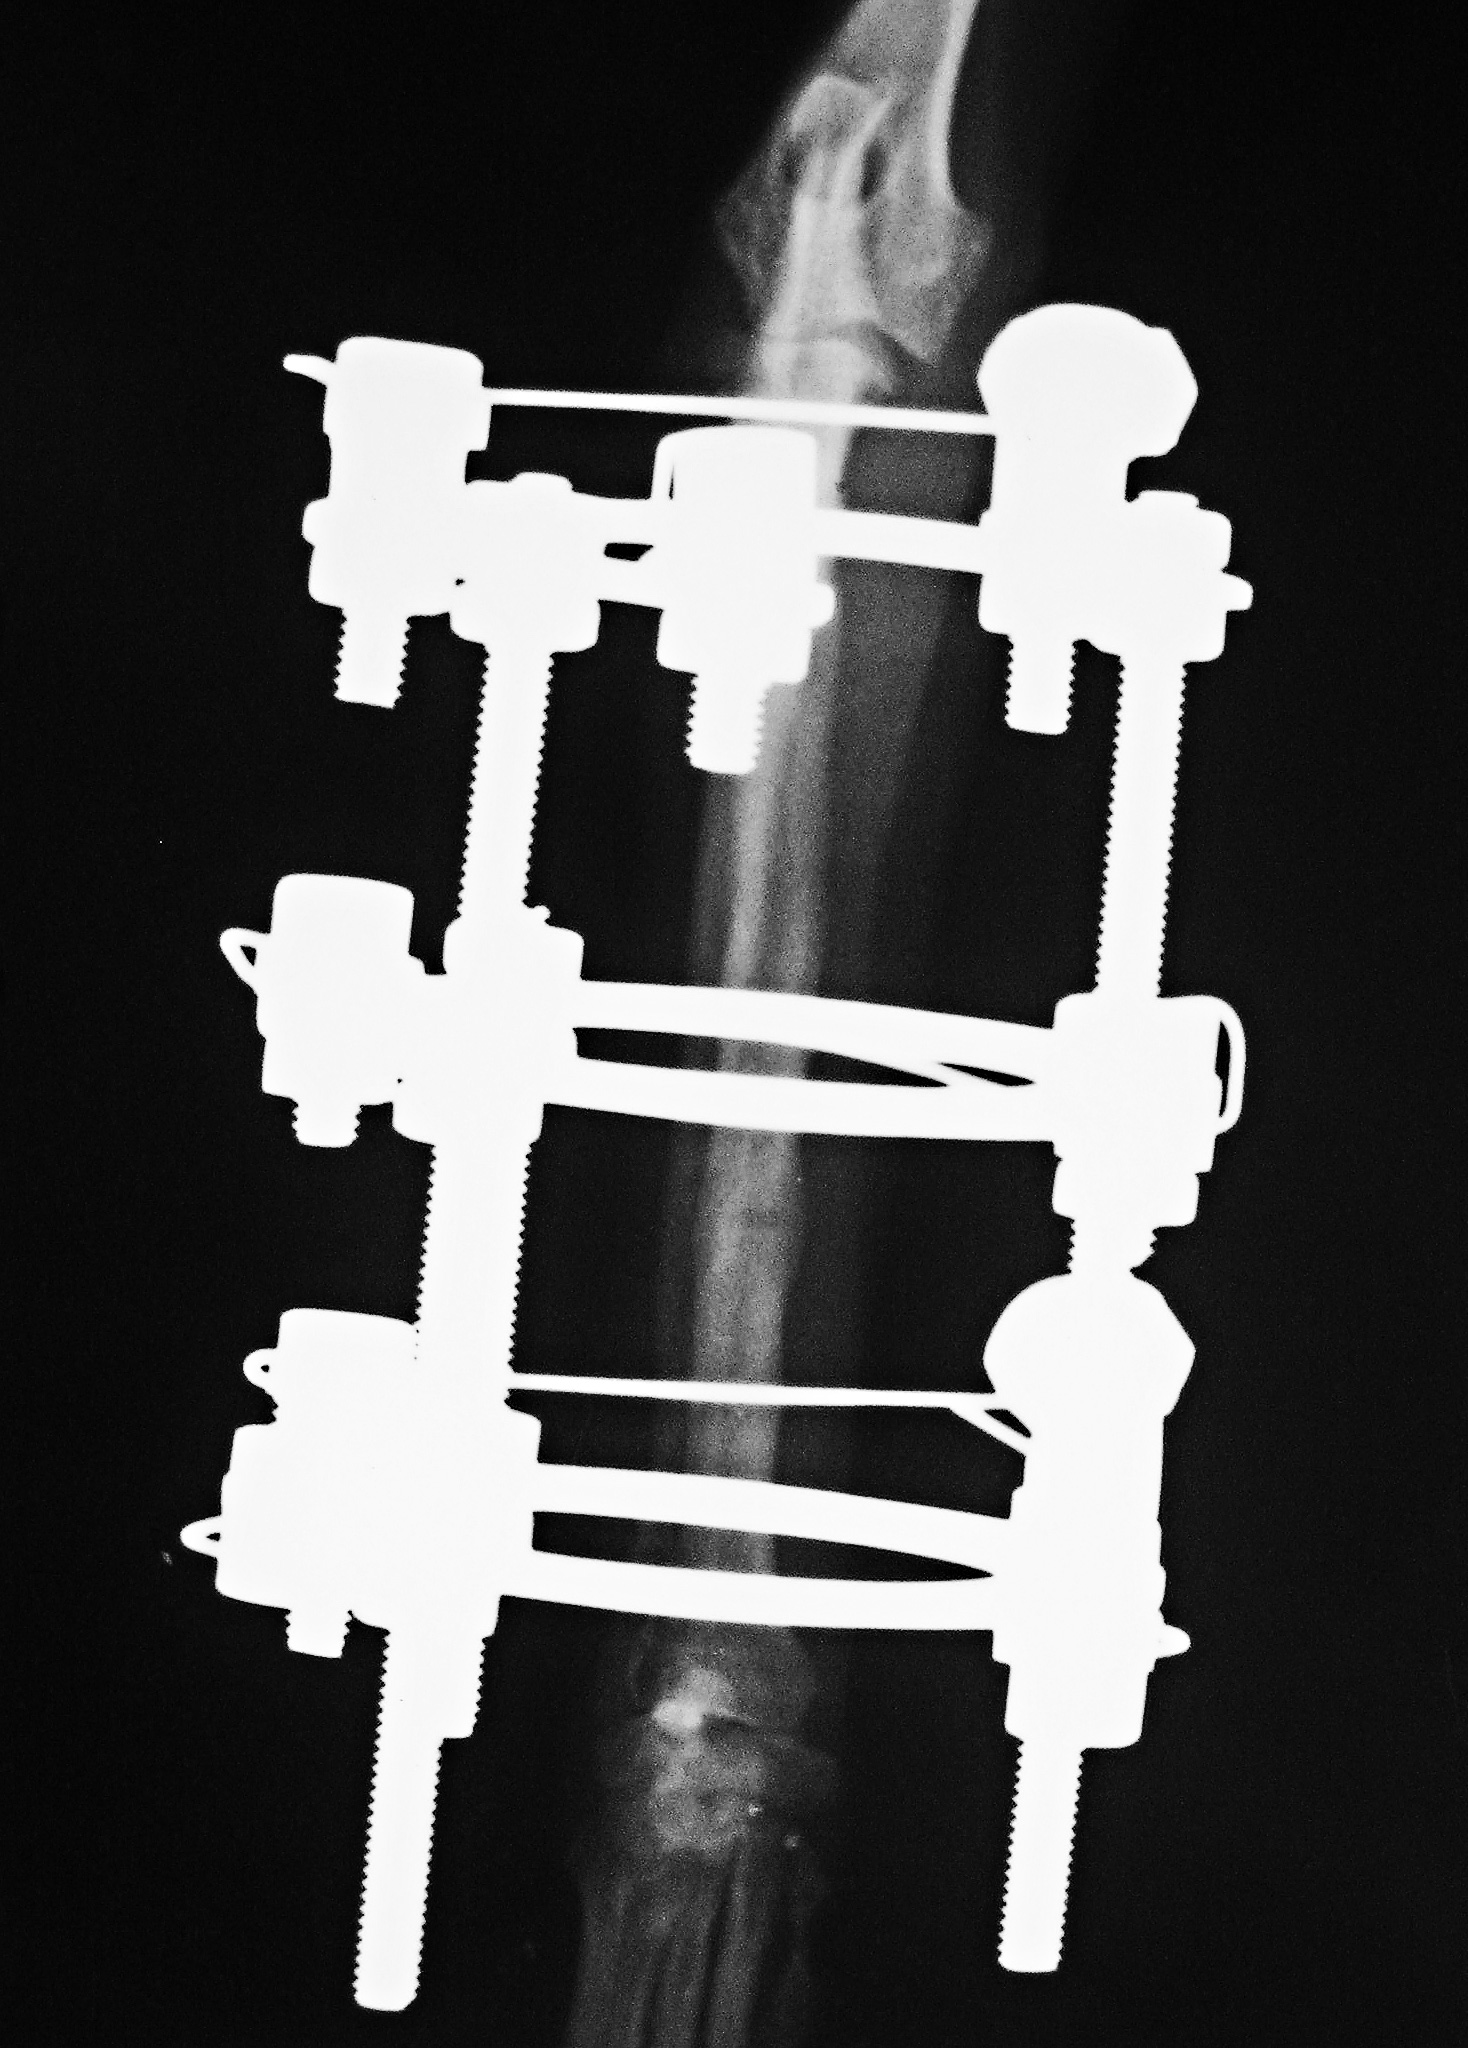

Аппарат Илизарова: принцип работы и применение

Раздел: Моменты озарения